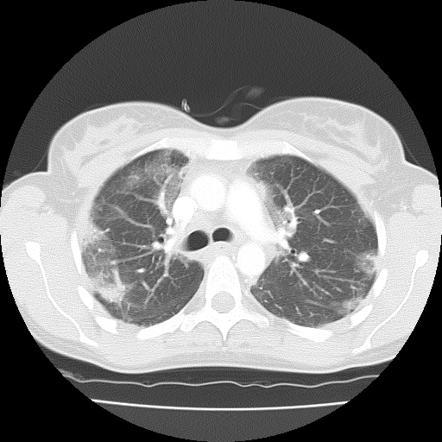

Ground glass opacities + fibrosis, lower lobe predominant, peripheral, fine reticulation. NO honeycombing

usu w/subpleural sparing, more symmetric

NSIP Pattern

Fibrotic type and cellular type, fibrotic more common

a/w CTD–esp dermatomyositis/polymyositis, sjogrens, SLE

anti-synthetase, RA, etc

Drug reactions esp chemo